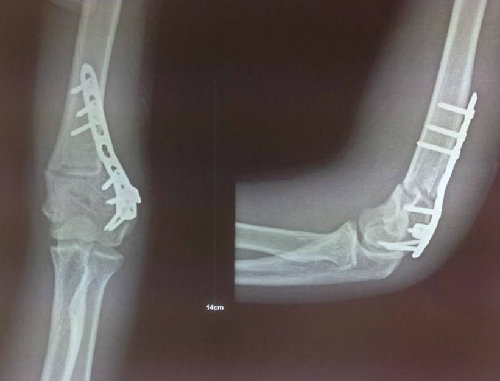

术后摄片

7月8日,由董谢平主任亲自操刀,在漆启华主治医师协助下顺利完成了肱骨髁上的截骨矫形,显露截骨部位,确定截骨角度后行左肱骨髁上外侧楔形截骨,保留内侧皮质完整,闭合外侧截骨面,并造成内侧皮质青枝骨折,钢板行后外侧固定。术中患肘即达到了较好的外观矫形,不但矫正了左肘关节内翻畸形,并让患者肘关节有10度左右的提携角。较以往截骨手术,手术时间大大缩短,出血量明显减少,外观矫形效果较前明显改善。